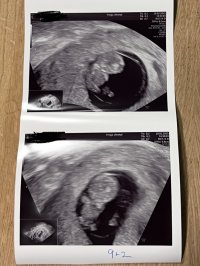

Vært så nervøs de to siste dagene pga brun utflod og lette kramper. Jordmor fant ingen synlig årsak, og konkluderte med at det mest sannsynlig kom av at morkaken tok over for plommesekken.

9+0, 178 bpm og 2,3cm lang. Perfekt liten miniatyrbaby som danset for oss på skjermen!